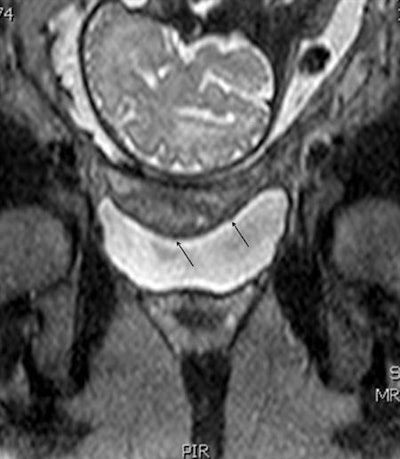

Standard MRI protocol included single-shot spectral-attenuated inversion-recovery (SPAIR) and single-shot T1- and T2-weighted inversion-recovery sequences in coronal and sagittal planes, as well as additional T2-weighted sequences in the axial plane.

All scans were performed after maternal hydration to achieve sufficient bladder filling for better tissue delineation, and protocols were optimized to ensure the highest possible signal-to-noise ratio (SNR) and finest spatial resolution. The researchers compared the imaging results with the operative findings.